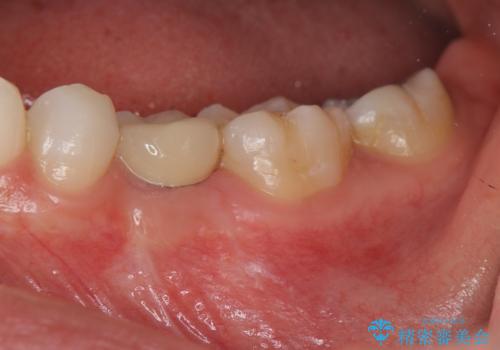

- 44万円(インプラント・チタンカスタムアバットメント・ジルコニアクラウン・仮歯)費用は治療当時の料金となります

乳歯の抜去後、インプラントを用いてしっかりと咬合機能を回復することができました。